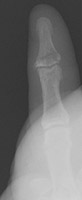

- Click on the image for a larger versionCOblique radiographs of the fourth PIP joint. This demonstrates apparent overriding of the proximal and middle phalanges.